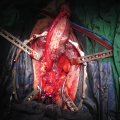

12.3.1.3 Augmented Anastomotic Urethroplasty

Guralnick and Webster [44] introduced the term ‘augmented anastomotic urethroplasty (AAU) ’ to describe a hybrid procedure combining elements of the EPA and substitution urethroplasty. Abouassaly and Angermeier [45] reported their experience of AAU in 69 patients with a success rate of 90% at a mean follow-up of 34 months. In 58 patients (84%) the graft was placed ventrally, whereas in 11 (16%) it was placed in the dorsal position. They found that recurrence tended to occur in older patients and in those with postoperative urinary tract infection. Hoy et al. [46] reported the results of 163 patients who underwent dorsal onlay AAU with BMG. The success rate was 96.9% with a median follow-up of 31 months. They suggested that strictures longer than 5 cm are amenable to repair using this technique, but are prone to recurrence. El-Kassaby et al. [47] reported the largest series using AAU with ventral BMG onlay. The success rate was 93.7% in 233 patients with a mean follow-up of 36 months. There was no comment on potential risk factors for recurrence.